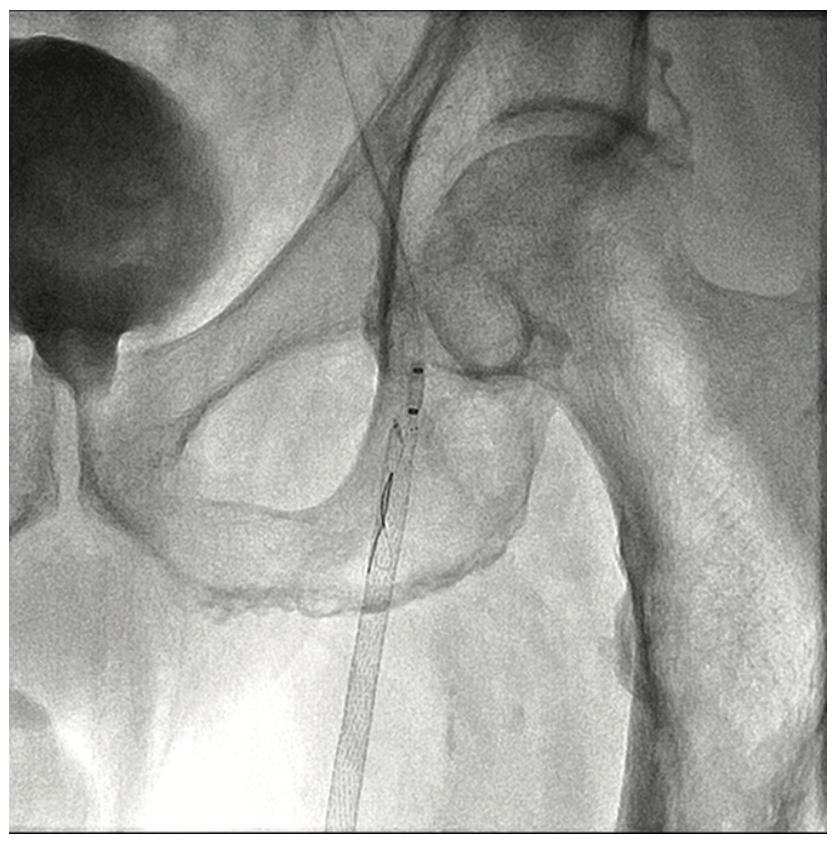

A 63-year-old male smoker presented with critical limb ischemia of his left foot. Four years prior, the patient underwent right fem-pop bypass after failed intervention on his right leg. He ended up losing the fifth digit on his right foot. Three years prior to his visit, he underwent a fem-pop bypass procedure on his left leg for severe claudication after failed intervention. One year later, he underwent a redo fem-pop on his left leg with a cadaveric vein. Twelve months prior to the visit, a self-expanding stent was placed in that fem-pop graft because of continued foot ischemia. Seven months prior to his visit, his symptoms re-occurred, and the patient was told nothing could be done after an angiogram showed the vessel was occluded. The patient suffered from polyneuropathy and was unable to walk, but did not want amputation. The patient was on cilastazol and coumadin, and had type II diabetes mellitus. His exam revealed a cool and red left foot, but no ulcers. Capillary filling was adequate. The right dorsalis pedis was normal, and there was no popliteal pulse on either side and no left pedal pulses. A contralateral approach was utilized and revealed the graft was occluded on the left side (Figure 1). The patient likely had thrombus in the graft, and we felt that a laser would be appropriate, used either in the traditional manner or with the step-by-step method. Whenever the step-by-step method is utilized, we use the CrossLock LP device (Radius Medical) for centering (Figure 2). The CrossLock LP is usually utilized for infrapopliteal lesions, but in this case, the 3 mm elastomeric balloon would fit well into the nub of the bypass graft. We immediately subtended the bypass graft all the way down and then were able to access the infrapopliteal vessels (Figures 3-4). We performed .9 mm laser (Spectranetics) in the graft and balloon angioplasty (Figure 5). Two Xience stents (Abbott Vascular) were placed, a 4.0 cm and 3.5 cm, at the anastomosis site, and because of residual stenosis at the popliteal, we placed a 5.5 cm Supera stent (Abbott Vascular). Due to multiple failures of the graft, the graft was covered with a 6.0 mm x 250 mm Gore Viabahn stent graft (W.L. Gore & Associates). At the end of the procedure, we were able to achieve brisk 2-vessel runoff (Figures 6-7). Fluoroscopic time was long at 73 minutes and the contrast utilization was 236 mL.